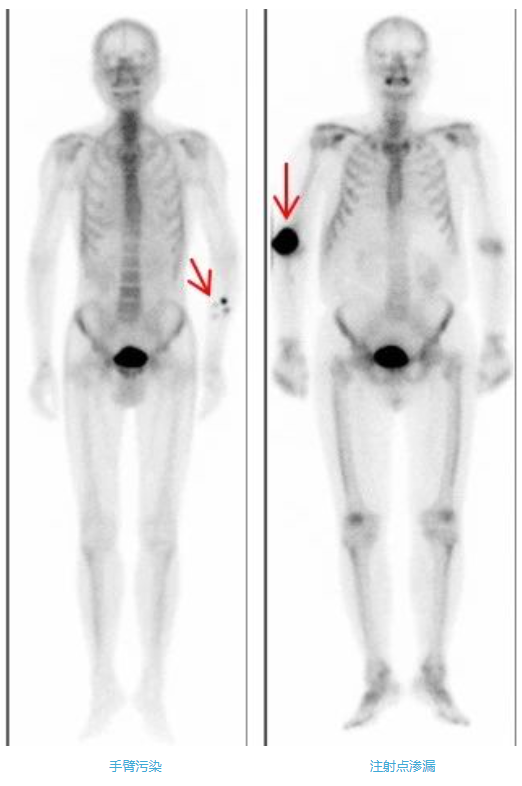

3、正確按壓注射點

當您一側上肢骨有癥狀時,要提醒護士在對側的血管注射。拔針后,需要您對針眼處稍用力按壓約5-10分鐘,按住不要揉,否則會造成注射部位異常放射性濃聚影,影響圖像質量。如果按壓的手指被血液或注射液污染,要及時沖洗,不要污染衣物或皮膚。